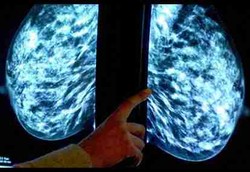

Cegah Kanker Payudara dengan Pare

Pare, sayuran dengan rasa pahit ini mempunyai khasiat yang menakjubkan. Pare ternyata dapat melindungi perempuan dari bahaya kanker payudara.